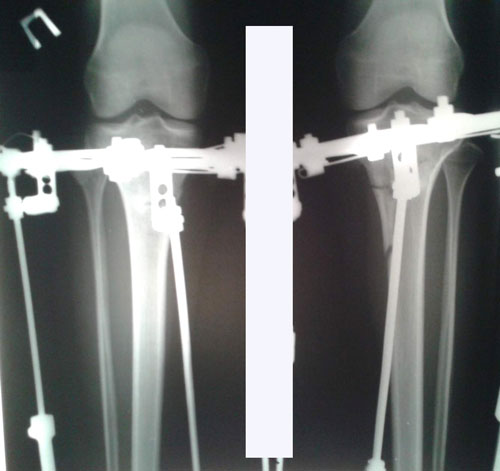

Поздравляю! Ура! Результат отличный!Sekretar Onipko писал(а):Рентген в 58 дней.

Сращение отличное, через неделю снимаем аппараты.